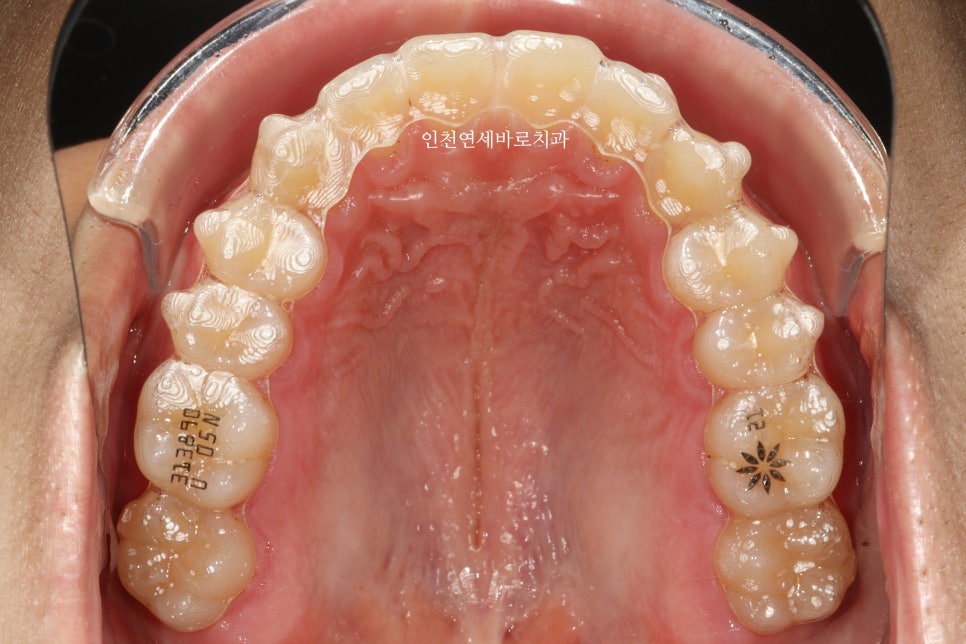

약 한달 정도 치료가 진행된 모습입니다.

인비절라인 장치를 보면 번호가 써 있습니다.

위 사진도 확대해서 어금니쪽을 보면 05 라고 써있죠

다섯번째 장치라는 표시입니다

인비절라인 장치에 있는 숫자는 무엇인가요?

인비절라인 장치에 표기된 숫자는 치료 단계를 나타내는 번호입니다. 예를 들어 ’05’는 다섯 번째 장치임을 의미하며, 환자는 순서대로 장치를 교체하여 치료를 진행합니다.